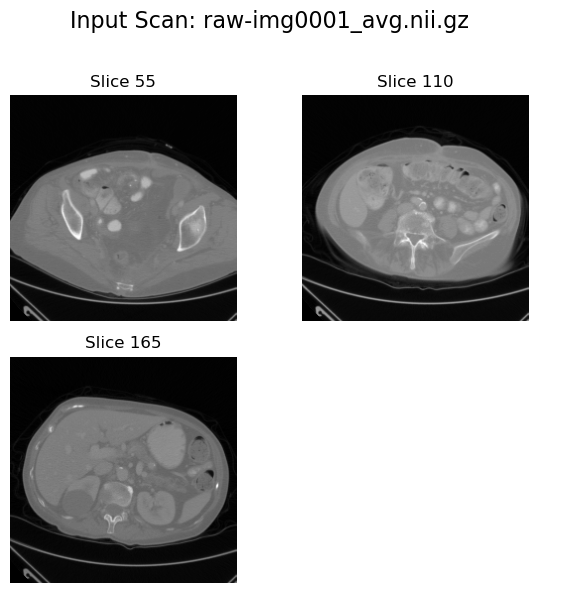

Input view#

plot_input_scan(input_path=image_path, num_slices_to_plot=3)

2025-08-04 10:51:49,784 - INFO - Input data shape: torch.Size([229, 229, 220])